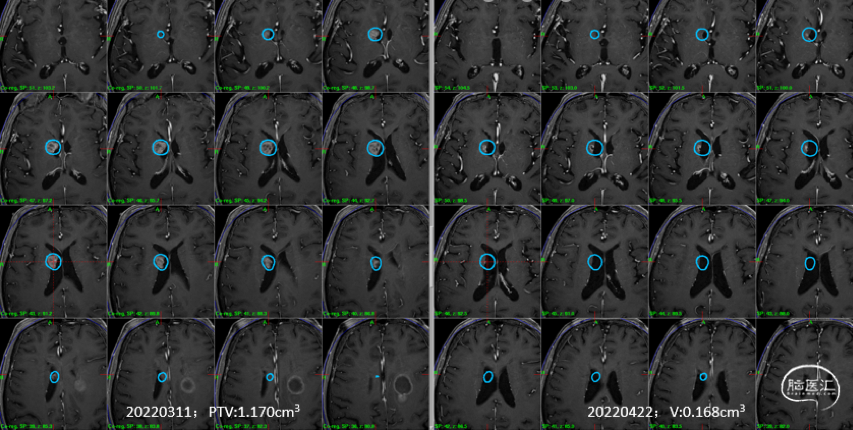

2)右侧侧脑室壁病灶体积缩小显著:

影像随访:

6个月随访时,薄扫增强磁共振(1mm/层)提示肿瘤明显缩小,无放射相关不良反应,没有新发病灶;患者目前仍在规律的随访当中,期待我们的长期随访结果。